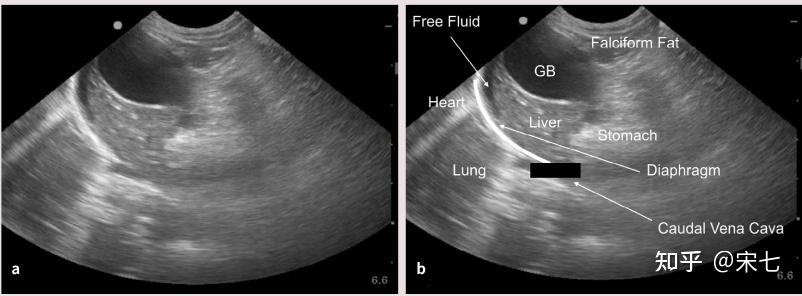

猫传腹(fip)的影像诊断

图片尺寸808x304